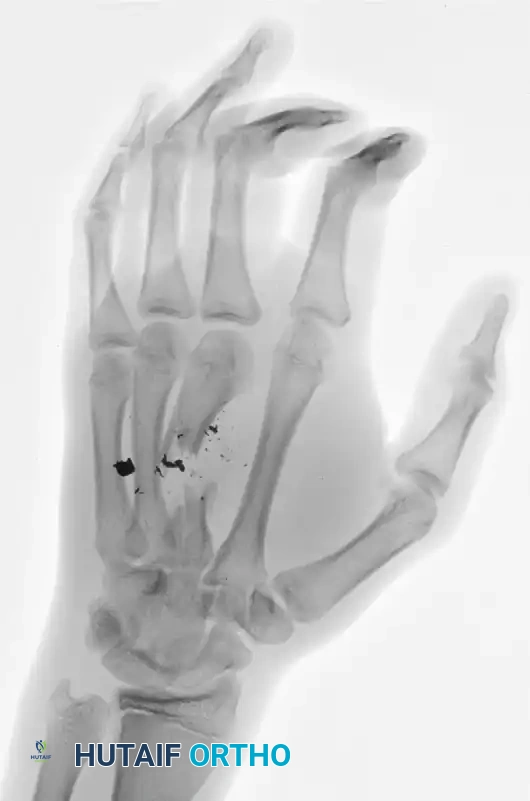

FIGURE 67-4 A and B: Comminuted middle finger metacarpal shaft fracture with intercalary bone loss from a self-inflicted handgun injury in a 17-year-old boy.

Figure 67-4 B: Oblique radiograph confirming the extent of the intercalary defect and the disruption of the longitudinal arch of the hand.